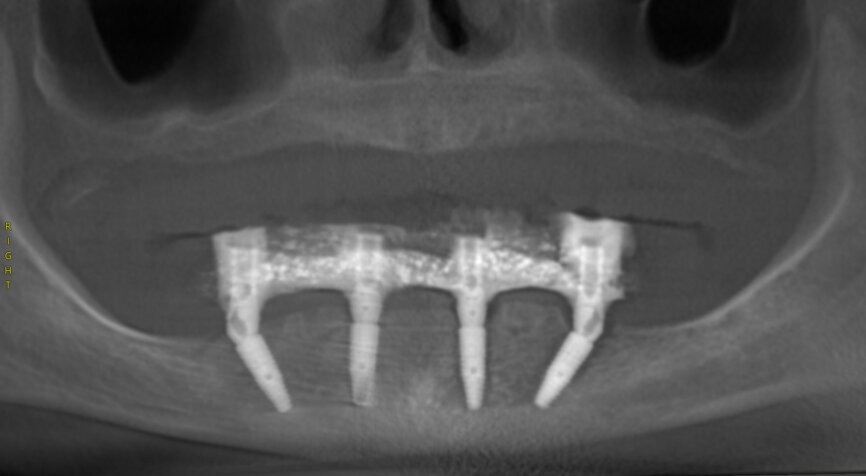

On the same day of the surgery, the existing denture was converted into an immediate temporary fixed restoration by adjusting it on temporary abutments directly in the mouth (Fig. 22), and an impression was taken as a double- check. The restoration was tightened to 15 Ncm (Fig. 23). Ten days later, the sutures were removed, the control CT scan was recorded (Fig. 24) and the results were assessed with the coDiagnostiX evaluation tool.